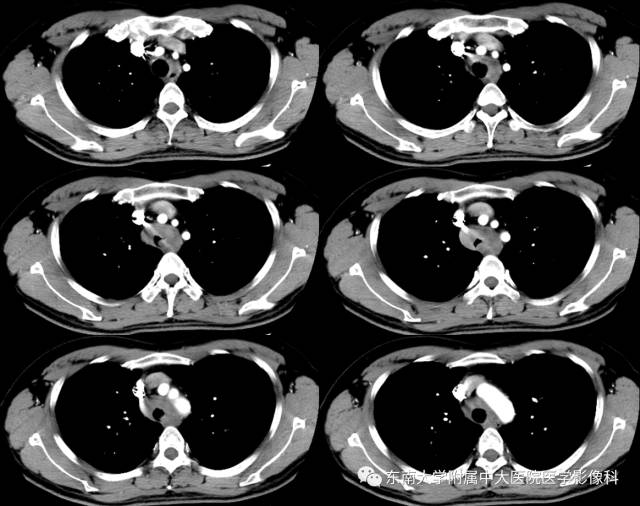

病例1

病史

男,35岁,因“反复咳嗽气喘1年余”入院。1年余前出现咳嗽气喘,咳嗽为阵发性干咳,感冒后加重,气喘多为活动后出现,自诉能听到哮鸣音。肺功能示:FVC%Pred 40%、FEV1%Pred 19%、FEV1/FVC% 80.9%,混合性通气功能障碍,支气管舒张试验阴性。

CT

平扫 增强